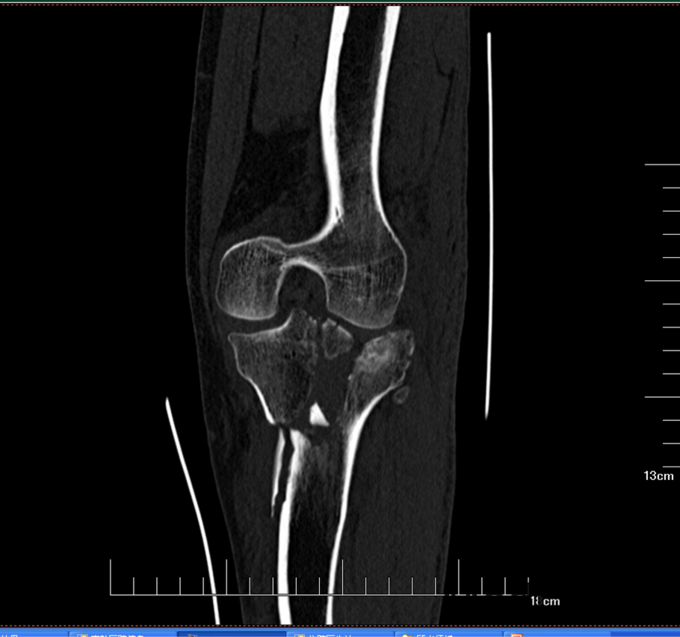

主诉:左膝关节外伤后疼痛12小时 现病史:患者男,61岁自述2014-7-4日走路时不小心滑倒,摔伤左膝关节,受伤后左膝关节疼痛、肿胀、无法活动,家人发现后送到当地医院,行拍片检查后,诊断为“左胫骨平台骨折”,并给予夹板固定左膝关节,建议转院治疗,为求进一步治疗来我院急诊,,我科以“左胫骨平台骨折”为诊断收入院,患者自受伤以来,无发热,无呼吸困难,无腹痛腹泻,饮食睡眠正常,大小便未见异常。

患者平车入病房,左膝关节夹板固定中,打开夹板,可见左膝关节肿胀,红肿,左膝部压痛(+),骨擦音及骨擦感(+),左下肢感觉未见异常,左膝关节活动不能,左踝关节及足趾活动正常,右下肢感觉运动正常,双侧足背动脉搏动可触及。

诊断:左胫骨平台骨折(Schatzker 6型) 患者入院后见患肢肿胀明显,给予患肢抬高位,冷敷,甘露醇消肿等对症治疗,带患肢出现褶皱试验阳性后,全麻下行左胫骨平台骨折切口复位钢板内固定术,术后患者肿胀明显,给予抗炎,消肿,冷敷,患肢抬高等对症治疗。患者每天换药观察切口愈合情况,无红肿及渗出,待伤口14天后予以拆线治疗,予以出院,给予康复处方。

患者胫骨平台6型骨折,根据三柱理论,应预约外侧平台,内侧平台,及后侧平台骨折,但是手术风险性大,尤其是后内侧行倒L行切口,需要避开重要的神经及血管为难点,还有就是患肢的肿胀情况,因固定了3块钢板,皮肤张力大,所以术后应注意患肢的血运及情况。 随访2个月后的DR可见骨折线模糊,骨痂生长明显,嘱患者术后3个月后可拄拐下地行走。